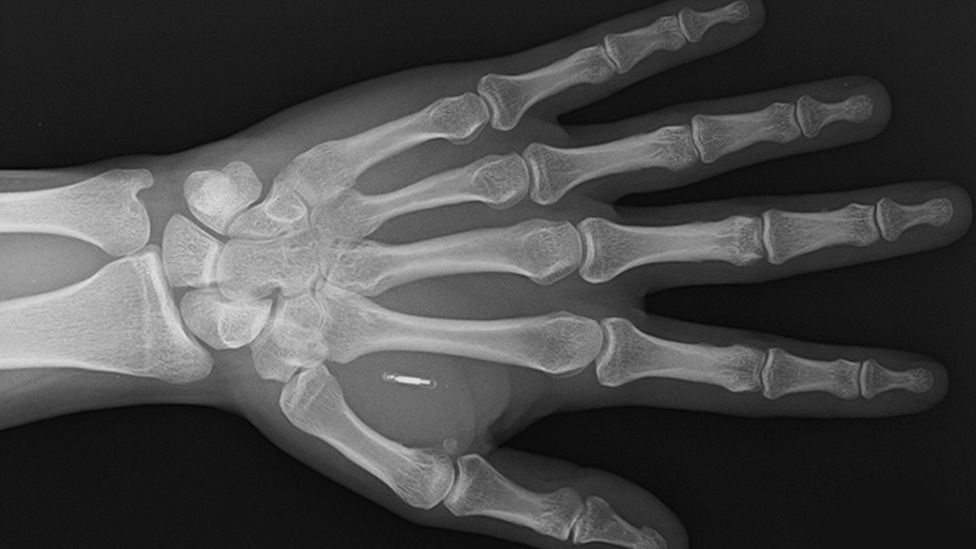

A tiny microchip and an antenna are enclosed in a biopolymer - a naturally derived material comparable to plastic - in Walletmor's chip, which weighs less than a gram and is about the size of a grain of rice.